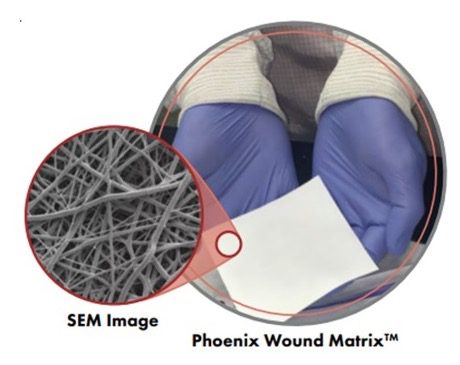

FG-0004 Size: 2.5cm x 2.5cm – Phoenix Wound Matrix 2.5cm x 2.5cm

- The Phoenix Wound Matrix®, a fully resorbable, 3D electrospun device composed of synthetic polymers, is designed to provide a temporary microenvironment that supports endogenous wound healing, allowing for regeneration and remodeling of native tissue in the defect space/wound bed. This device is engineered to promote healthy tissue growth rather than a protracted inflammatory response.†

- For over a decade, Nanofiber Solutions, the technical parent company of RenovoDerm®, has worked with progressive surgeons and researchers to develop products designed to mimic the in vivo, microscopic, physical structures and properties of the extracellular matrix (ECM) vital to functional tissue regeneration.